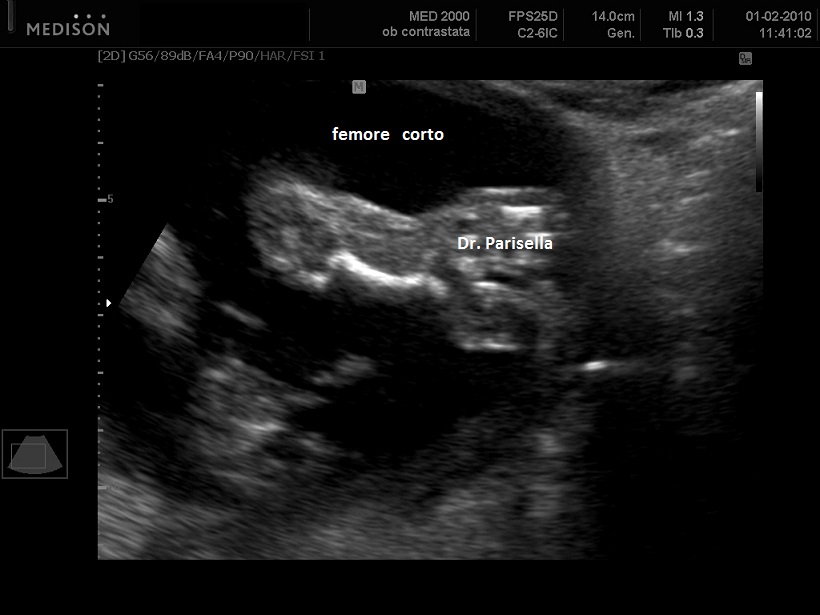

La condrodisplasia puntata rizomelica ha una prevalenza stimata in 1:100.000. E' caratterizzata da nanismo che colpisce soprattutto il tratto rizomelico ( femore e omero ), tipico aspetto del viso (ampio ponte nasale, epicanto, palato ogivale, orecchie esterne displasiche, micrognazia)  alterazioni vertebrali, cataratta, lesioni cutanee e grave ritardo mentale. Le alterazioni vertebrali consistono caratteristicamente in lesioni coronali dei corpivertebrali. La malattia è causata da un difetto del metabolismo dei perossisomi e viene trasmessa come carattere autosomico recessivo.

La Condrodisplasia Puntata legata all'X Dominante o Sindrome di Conradi-Hünermann può essere diagnosticata in epoca prenatale, di solito nel III trimestre. E' caratterizzata da bassa statura legata ad ipoplasia di omero e femore (l'omero è colpito principalmente), asimmetria degli arti, scoliosi, epifisi slargate con multipli foci iperecogeni, contratture articolari; segni presenti ma non evidenziabili all'ecografia sono l'eritroderma ittiosiforme lamellare e la cataratta, che può essere monolaterale. L'intelligenza è normale. La malattia colpisce prevalentemente le femmine ed è più grave o addirittura letale nei maschi. È trasmessa come carattere dominante legato all'X, dovuta a mutazioni nel gene EBP che codifica per un enzima coinvolto nel metabolismo del colesterolo.